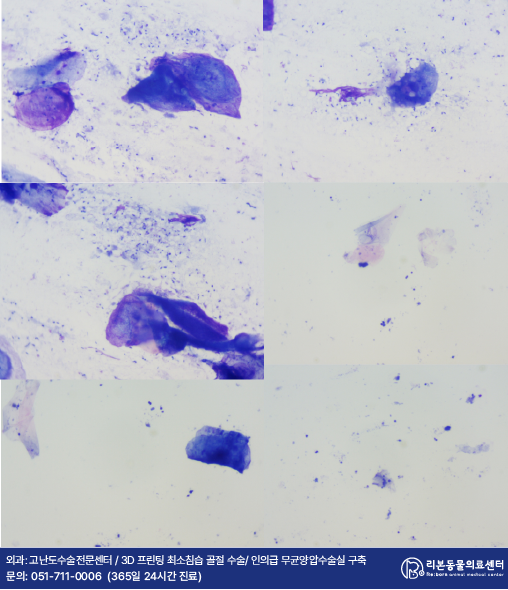

관찰되는 귀지를 채취하여 진행된 도말 검사 상에서는 좌측 귀의 세균 감염, 우측 귀의 진균과 세균의 동시 감염이 관찰되었습니다.

세균 배양 상 세종류나 되는 세균이 검출되었고 그 중 한 종류는 대다수의 항생제에 강력한 내성을 보였습니다.